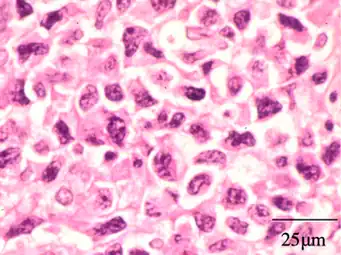

Histology

On histologic examination, nasal polyps consist of hyperplastic edematous (excess fluid) connective tissue with some seromucous glands and cells representing inflammation (mostly neutrophils and eosinophils). Polyps have virtually no neurons. Therefore, the tissue that makes up the polyp does not have any tissue sensation and the polyp itself will not be painful.[6] In early stages, the surface of the nasal polyp is covered by normal respiratory epithelium, but later it undergoes metaplastic change to squamous type epithelium with the constant irritation and inflammation. The submucosa shows large intercellular spaces filled with serous fluid.[15]

-

Benign mixed inflammation of an inflammatory nasal polyp. -

Extranodal NK/T cell lymphoma, nasal type for comparison.[17] These lymphoma cells are typically monotonous, with folded nuclei, indistinct nucleoli and moderate amount of cytoplasm.[18]